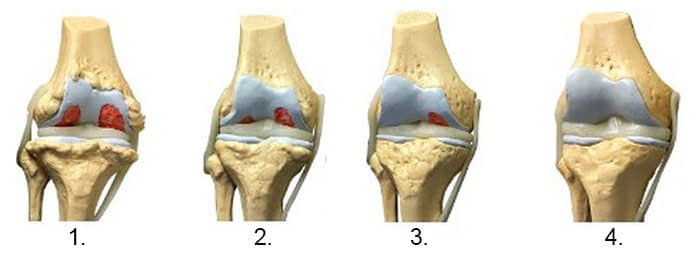

1. Pomanjkanje hranil v sklepih Tkivo hrustanca je skoraj povsem uničeno.

2. Obnovitev tkiva hrustanca po 2 tednih uporabe mazila Motion Free .

3. Obnovitev tkiva hrustanca po 3 tednih uporabe mazila Motion Free .

4. Zdrav sklep po zdravljenju z mazilom Motion Free .